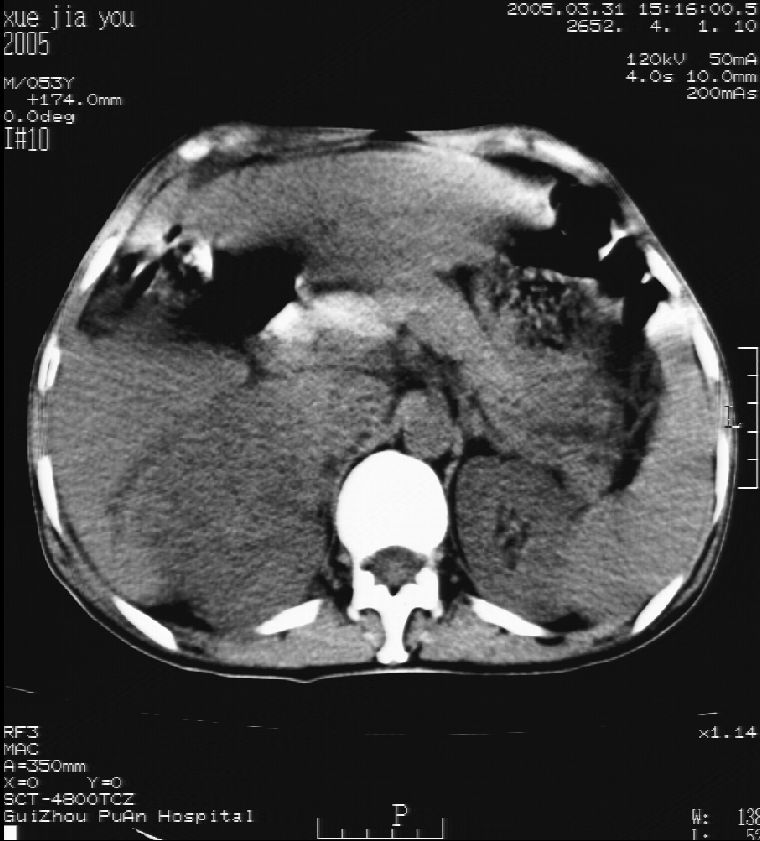

男 55岁  反复上腹痛1年,伴恶心呕吐。2005年做第一次检查后,到外院做b超检查提示肝囊肿,未做任何手术。2006年做过胆总管结石术。骨窗未见异常

这个病灶很有意思,怎么可能没有了呢?我考虑当时很可能是肝脏脓肿(b超示囊肿是有可能误诊的,因为影像表现都是低回声吗?),现在脓肿吸收了,肝脏萎缩,肝裂增宽了.别的肝叶代偿增大,不过现在左内叶的确有个占位,肝内多发结石,脾脏比以前大,不排除有肝硬化可能.建议增强扫描给于定性!!!!